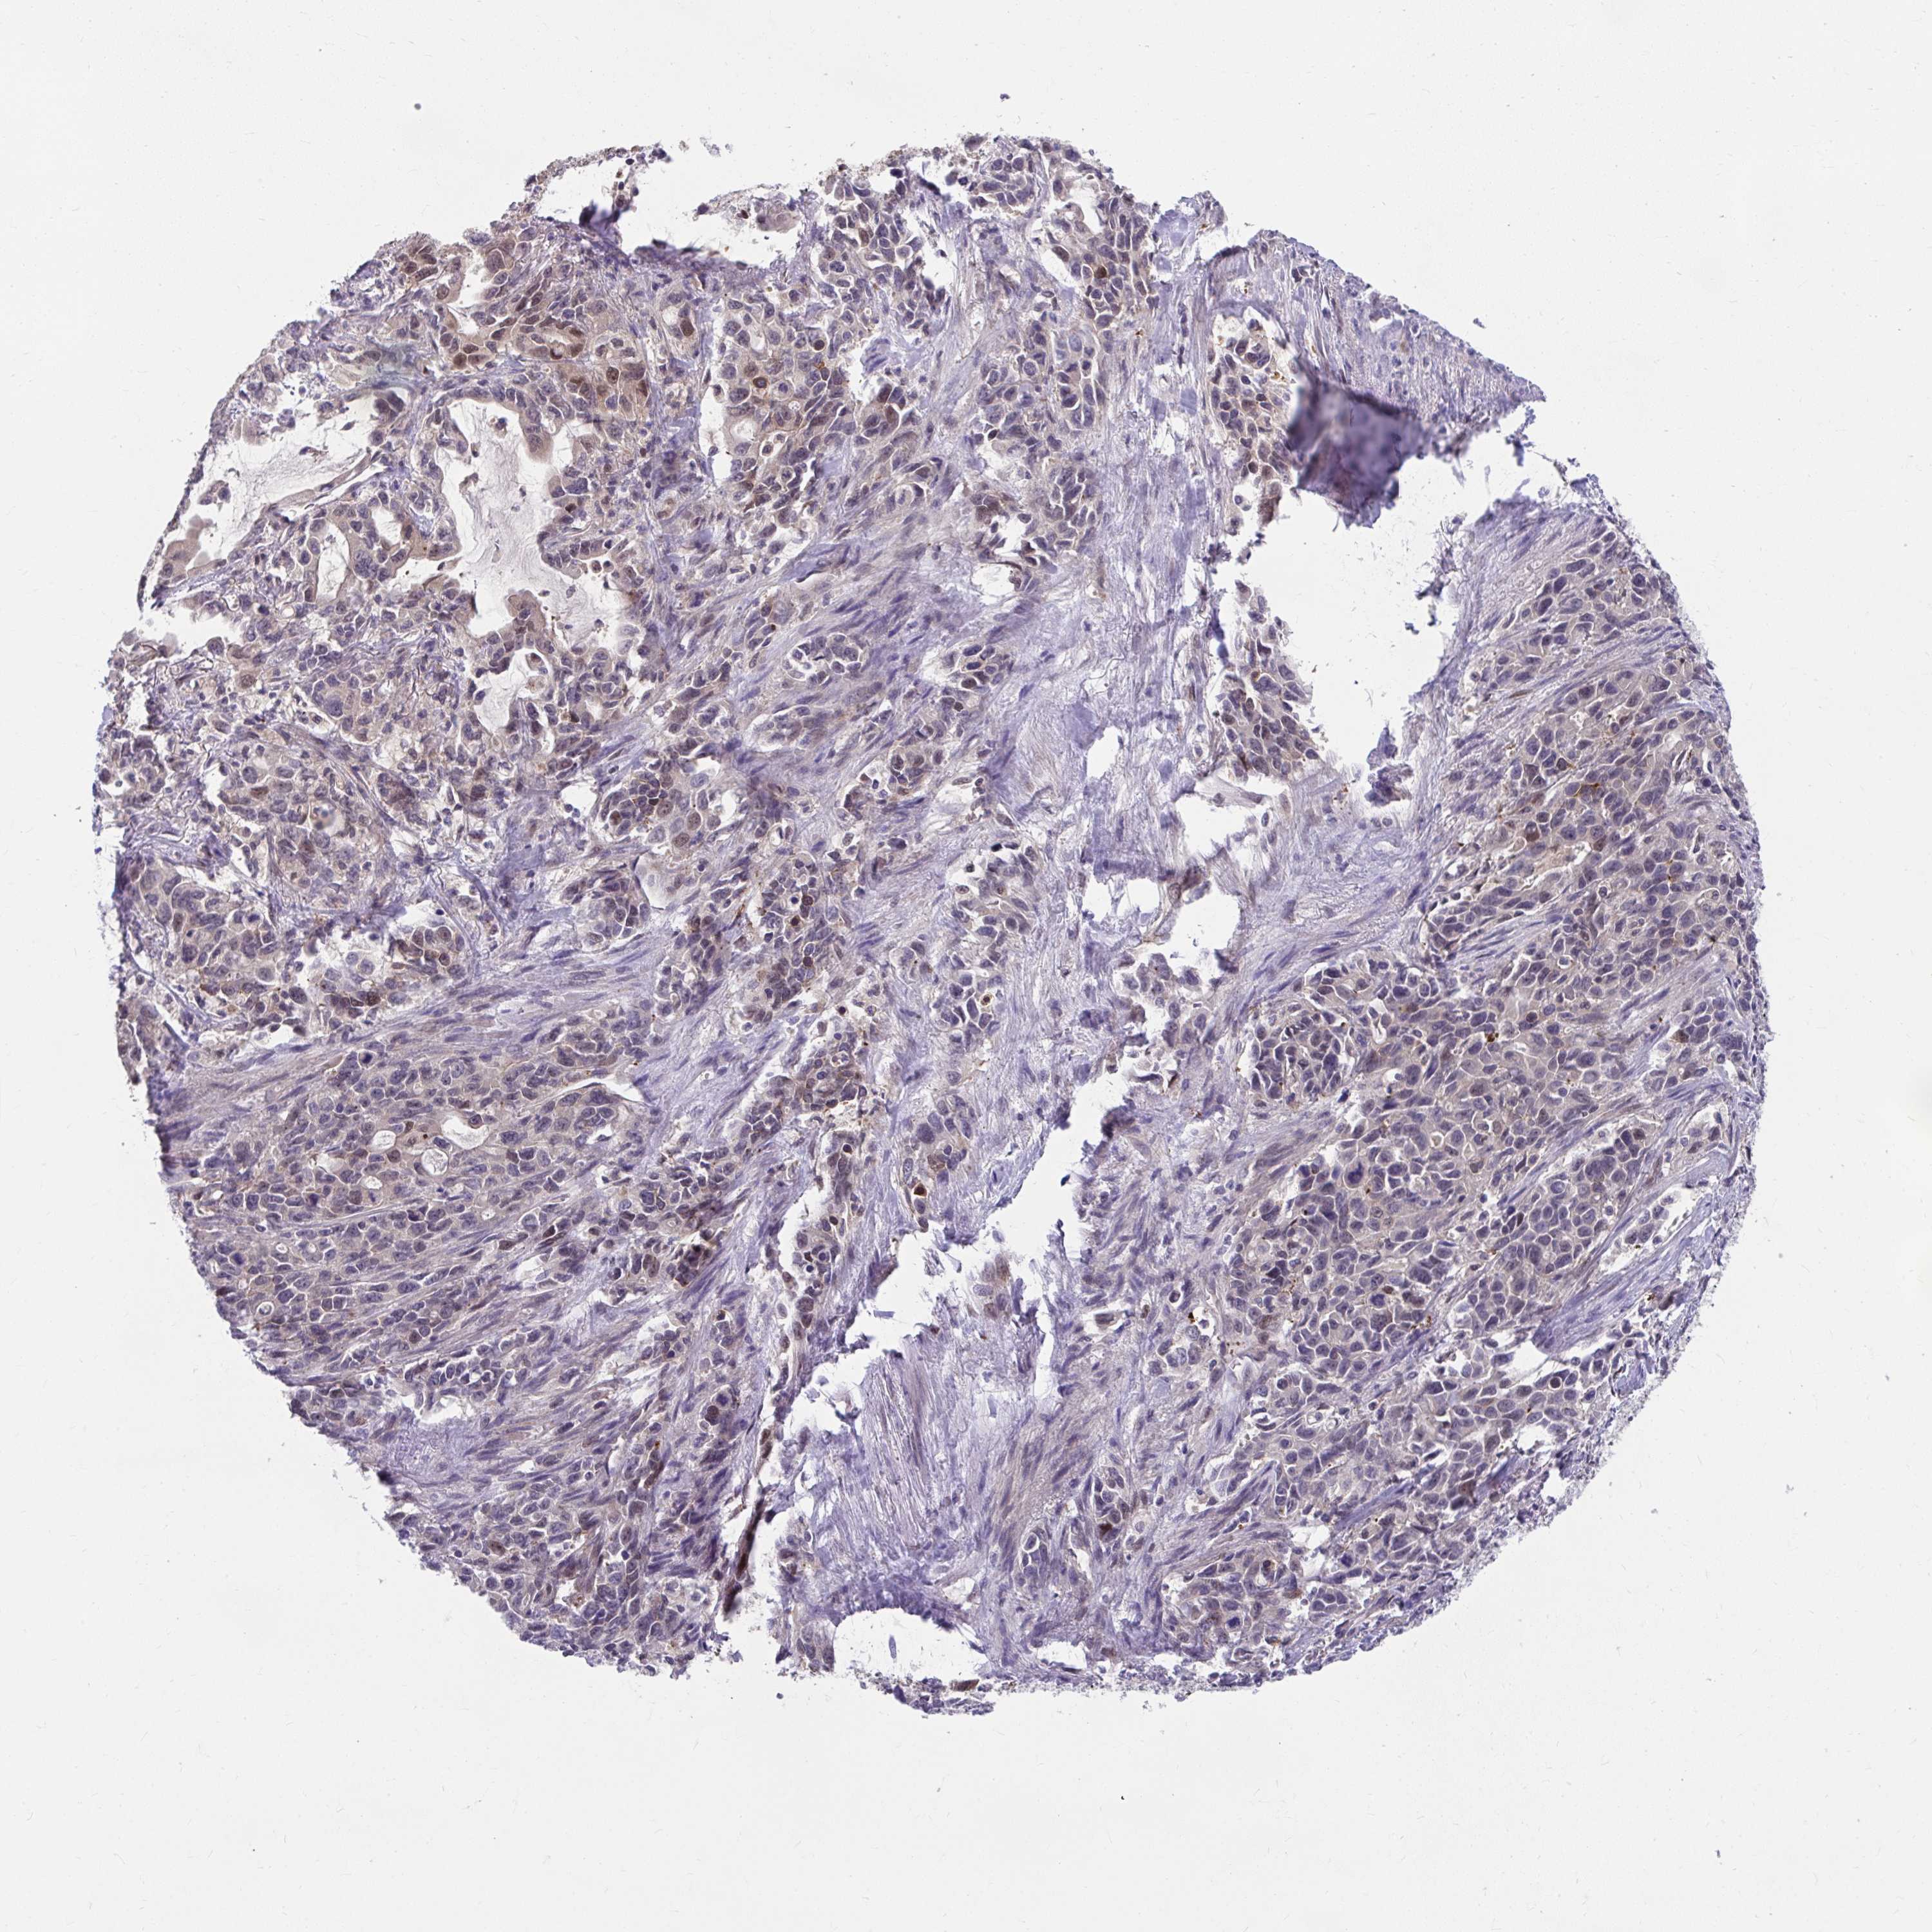

STOMACH CANCER - Protein expressioni

A mouse-over function shows sample information and annotation data. Click on an image to view it in a full screen mode. Samples can be filtered based on level of antibody staining by selecting one or several of the following categories: high, medium, low and not detected. The assay and annotation is described here.

Note that samples used for immunohistochemistry by the Human Protein Atlas do not correspond to samples in the TCGA dataset.

Antibody stainingi

Antibody staining in the annotated cell types in the current human tissue is reported as not detected, low, medium, or high, based on conventional immunohistochemistry profiling in selected tissues. This score is based on the combination of the staining intensity and fraction of stained cells.

Each image is clickable and will lead to virtual microscopy that enables deeper exploration of all samples and also displays staining intensity scores, fraction scores and subcellular localization as well as patient and tissue information for each sample.

Antibody HPA059271

Staining

High

Medium

Low

Not detected

Intensity

Strong

Moderate

Weak

Negative

Quantity

>75%

75%-25%

<25%

None

Location

Nuclear

Cytoplasmic/membranous

Cytoplasmic/membranous,nuclear

Adenocarcinoma, NOS